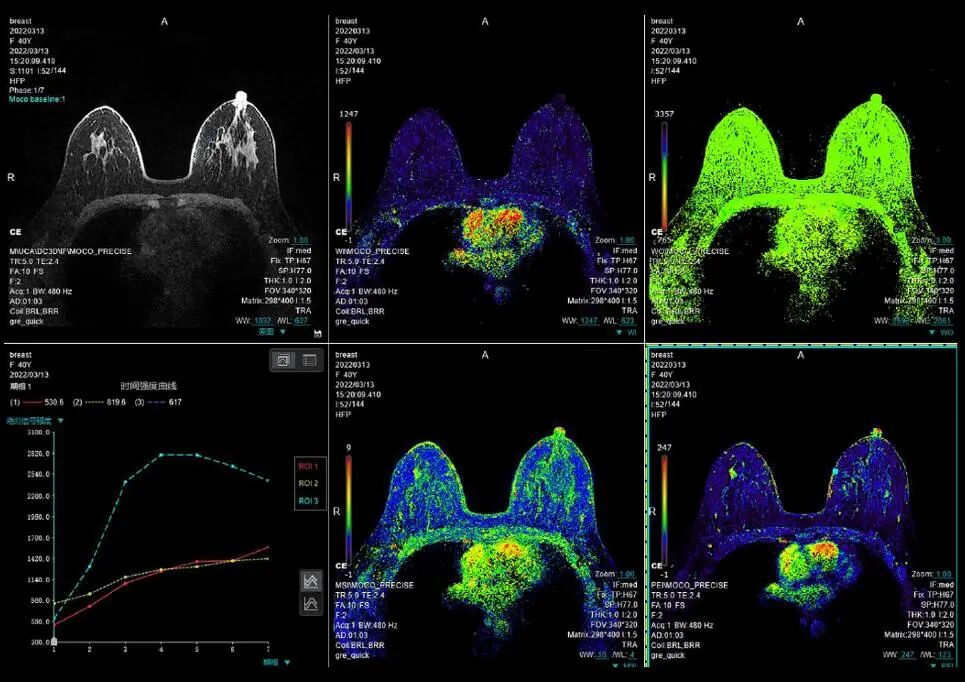

7.乳腺:对于早期发现的乳腺疾病及良恶性能够提供较明确的诊断。

uMR 870配备了丰富且强大的MR图像分析功能,包含了弥散分析、波谱分析、血管分析、斑块分析、乳腺分析、动态分析、脑灌注分析、联合神经分析、SWI+、DCE高级应用、Maps等。

联影磁共振怎么样更先进、更高效、更精准—联影3.0T超导磁共振落户武城县人民医院_https://www.jmylbn.com_新闻资讯_第19张